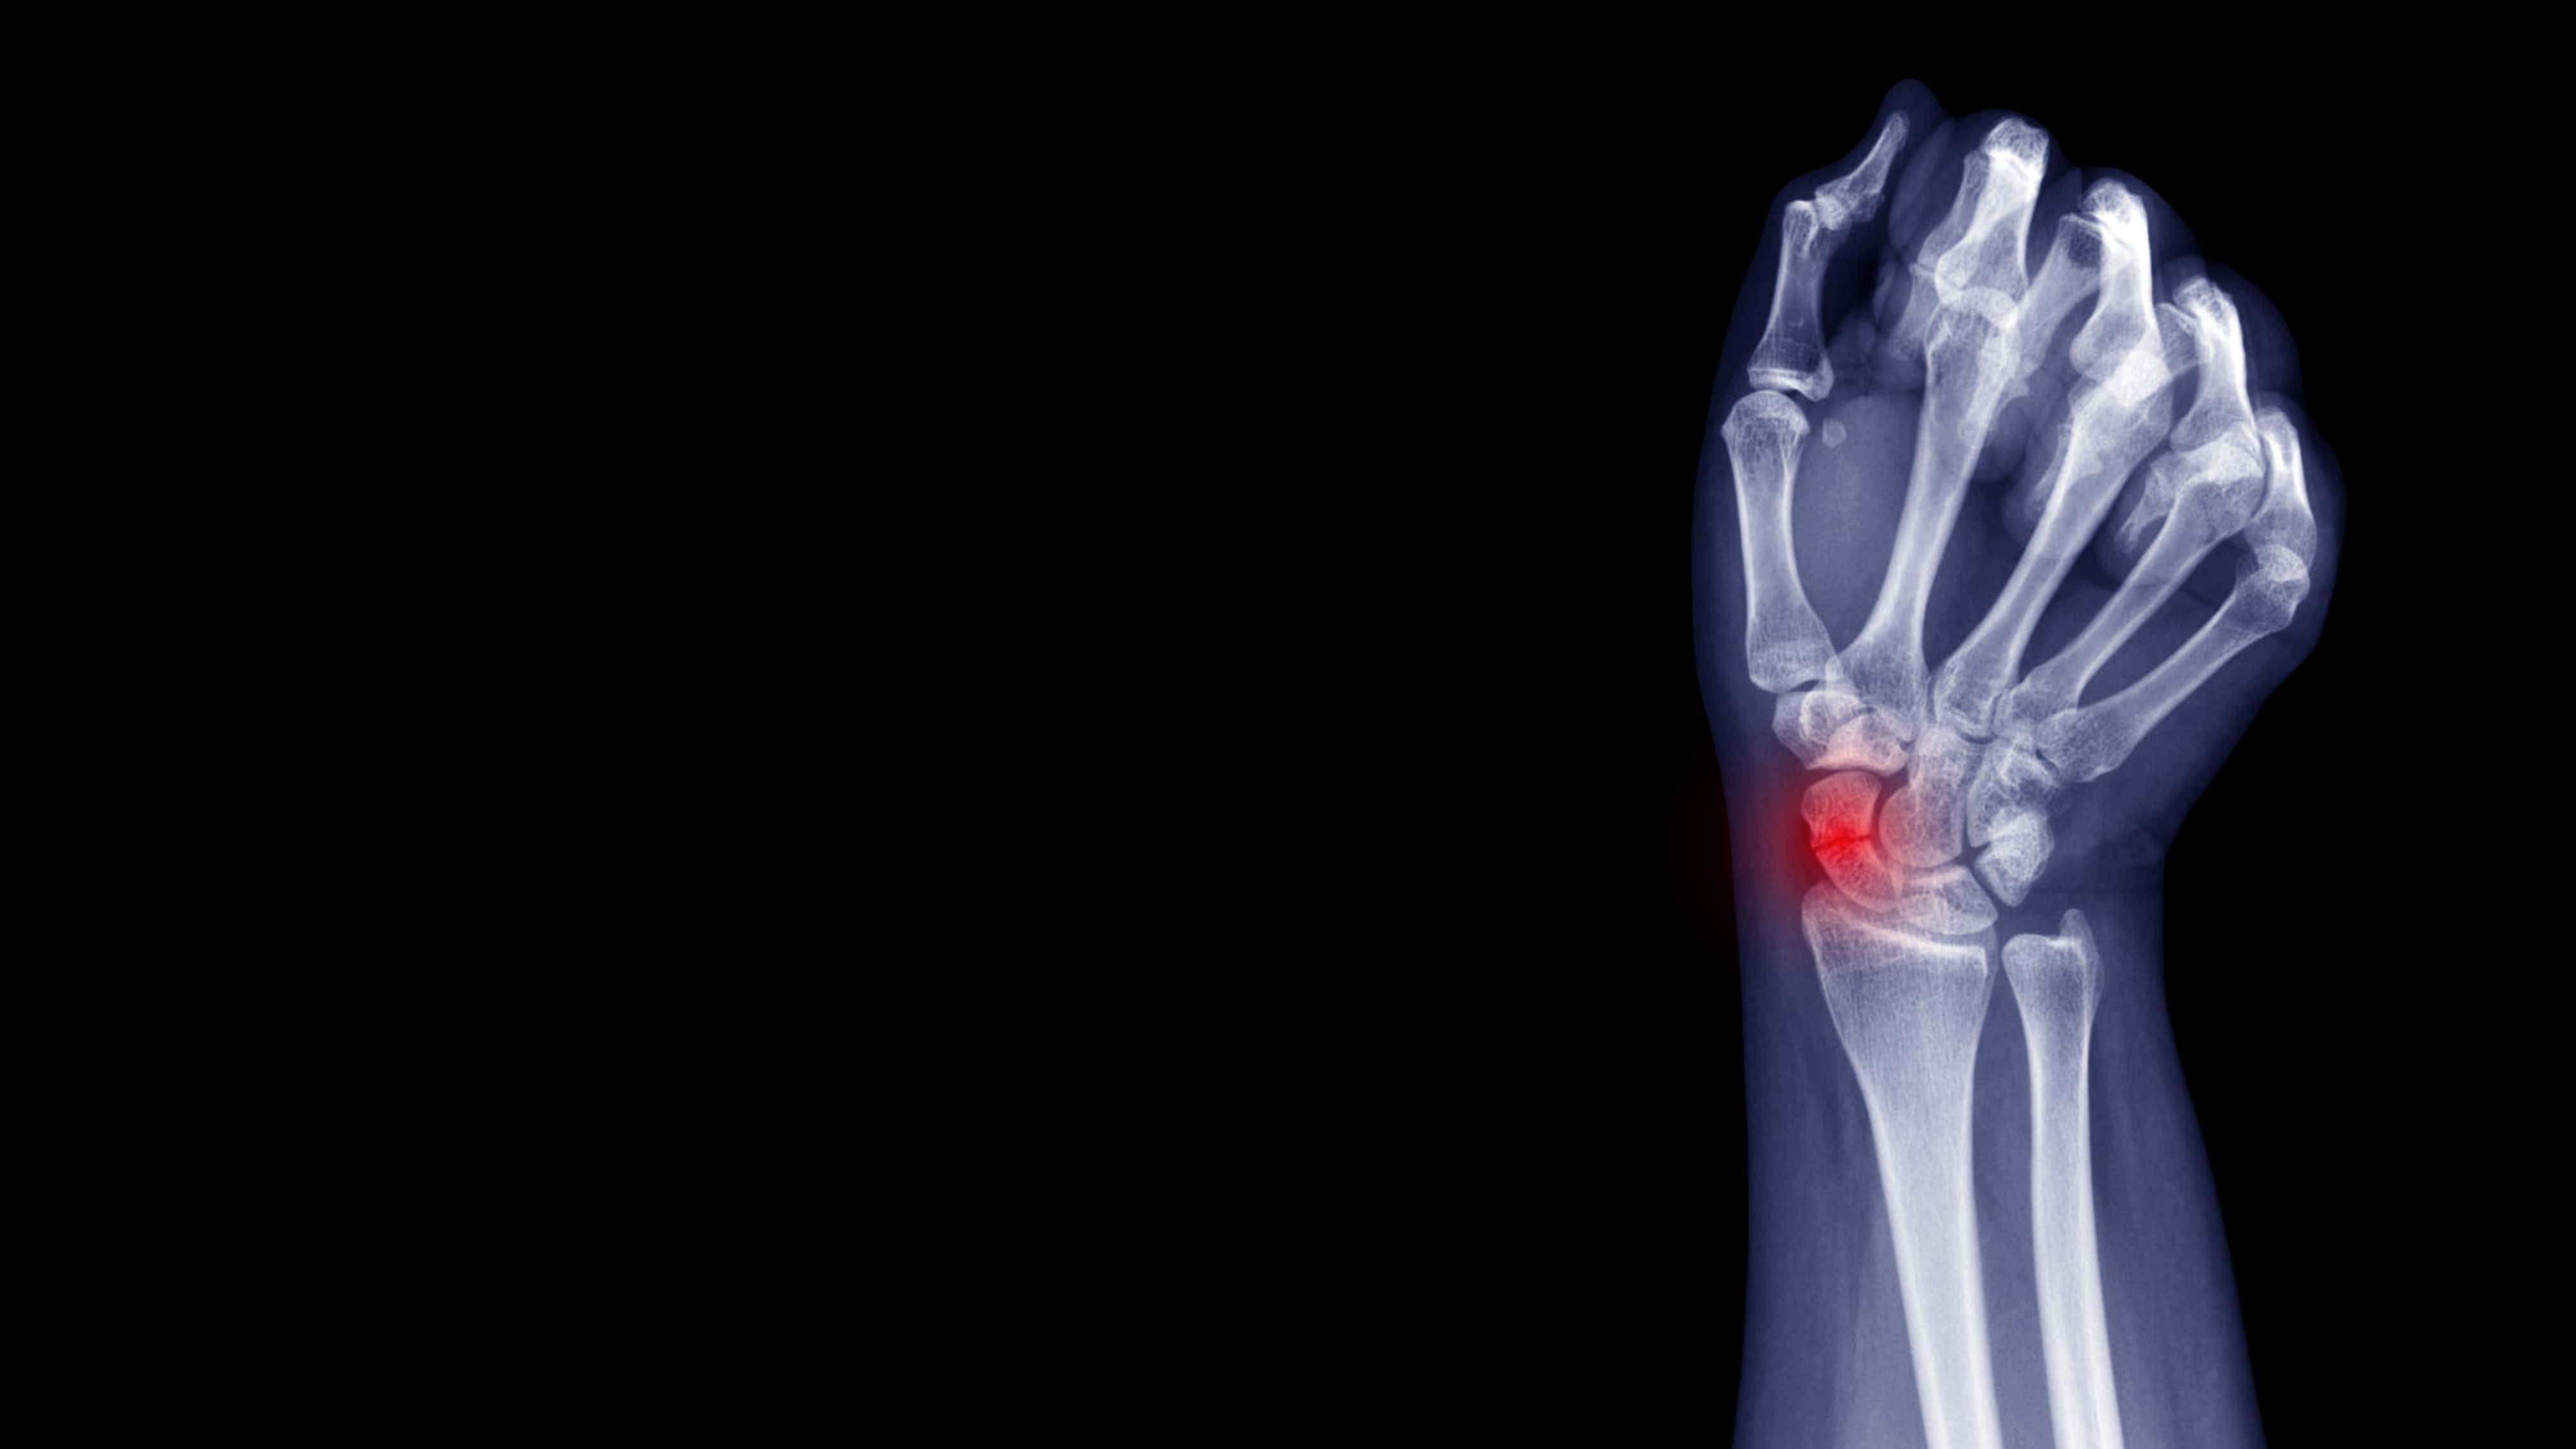

Wrist Scaphoid Fractures